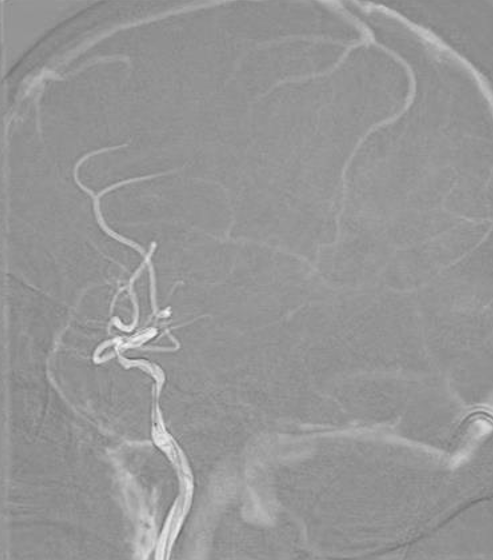

治疗过程

将 6F 导引导管送至 C3 段。

导丝怎么扩【载药时代 球扩天下】NOVA DES®颅内药物洗脱支架在颈内动脉颅内段重度狭窄中的应用体会二例!_https://www.jmylbn.com_新闻资讯_第24张

导引导管到位,导丝通过病变

通过微导丝携带球囊至狭窄段。

导丝怎么扩【载药时代 球扩天下】NOVA DES®颅内药物洗脱支架在颈内动脉颅内段重度狭窄中的应用体会二例!_https://www.jmylbn.com_新闻资讯_第25张

球囊通过病变

球囊到位后准确定位后缓慢扩张球囊。

导丝怎么扩【载药时代 球扩天下】NOVA DES®颅内药物洗脱支架在颈内动脉颅内段重度狭窄中的应用体会二例!_https://www.jmylbn.com_新闻资讯_第26张

球囊扩张过程

扩张后撤出球囊造影,见狭窄有所改善。

导丝怎么扩【载药时代 球扩天下】NOVA DES®颅内药物洗脱支架在颈内动脉颅内段重度狭窄中的应用体会二例!_https://www.jmylbn.com_新闻资讯_第27张

扩张后造影

通过导丝携带球扩支架到达病变位置。

导丝怎么扩【载药时代 球扩天下】NOVA DES®颅内药物洗脱支架在颈内动脉颅内段重度狭窄中的应用体会二例!_https://www.jmylbn.com_新闻资讯_第28张

支架通过病变

缓慢扩充球囊释放支架。

导丝怎么扩【载药时代 球扩天下】NOVA DES®颅内药物洗脱支架在颈内动脉颅内段重度狭窄中的应用体会二例!_https://www.jmylbn.com_新闻资讯_第29张

支架释放